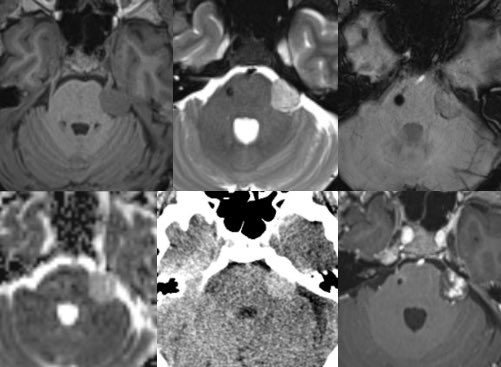

RJ

Every time I run a ZTE sequence for pars eval, I'm unimpressed and compared to thin 2-D sequencing, do not think it adds any value. Curious what others think now several years after the excitement has worn off.

RJ tweet mediaRJ tweet mediaRJ tweet media